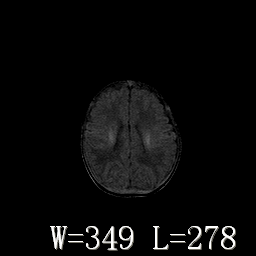

男,4天,发复抽搐1天。

hie?

脑干形态欠规则,信号增高,不知怎么解释?

脑干背侧面t1高信号是,新生儿正常已经髓鞘化好的部位